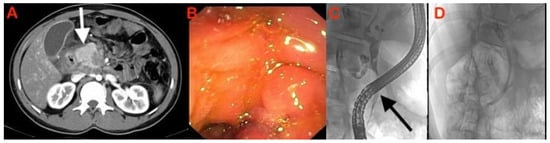

| Smooth narrowing of the pancreatic duct as it traverses through the mass without any abrupt cut-off is a reliable sign that it is inflammatory. The diagnostic accuracy of this sign is 94%. |

| Presence of side-branch dilatation is a reliable sign that the mass is inflammatory in nature. This phenomenon is hypothesised to occur due to the traction effect caused by interstitial fibrosis in chronic pancreatitis, rather than mass effect from a neoplasm where duct obliteration would be expected. |

| Simultaneous dilatation of both pancreatic and common bile ducts is an indicator of malignancy. It is seen in ampullary tumours and in 77% of the cases of pancreatic head malignancy; however, it is not exclusive to this, as it may also be seen in mass forming AIP as well as in other non-malignant conditions. |